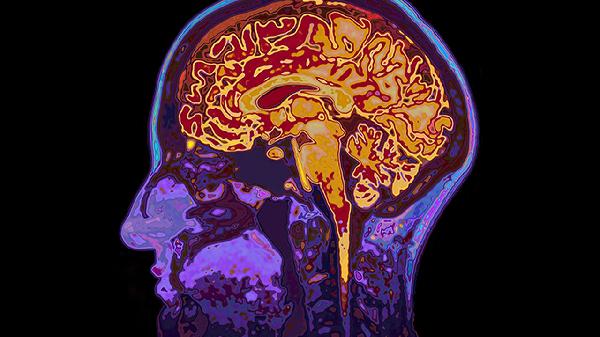

大脑脑萎缩可通过生活干预、物理治疗、药物治疗、手术治疗等方式治疗。脑萎缩可能与遗传、脑血管疾病、神经系统退行性变、外伤、感染等因素有关,通常表现为记忆力减退、认知功能障碍、运动协调能力下降等症状。